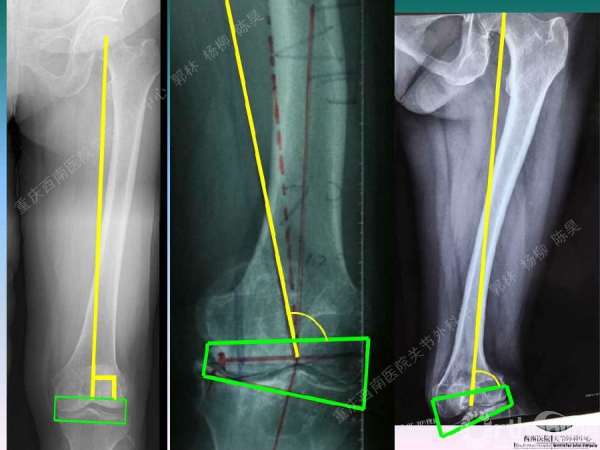

导读:文中,来自重庆西南医院的郭林教授为大家介绍了股骨冠状位关节外畸形的TKA的相关知识,并详细阐述了关节外畸形的概念、诊断、关节内滑移截骨技术等相关内容。

滑移截骨纠正关节外畸形